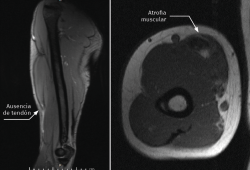

El paciente fue intervenido bajo anestesia axilar y con manguito de isquemia. El acceso único utilizado fue un Henry modificado extendido proximal y distalmente según las necesidades del caso.

La técnica de sutura del injerto de Aquiles fue la de tipo FiberLoop distalmente y anclamos el tendón mediante un botón cortical (EndoButton®, Smith & Nephew) en disposición intramedular en la tuberosidad bicipital del radio para evitar el riesgo de lesión del nervio radial. La sutura proximal fue mediante puntos de tipo Krakow intentando envolver el muñón muscular en toda su circunferencia utilizando la parte proximal del tendón de Aquiles como un abanico desplegado (Figuras 2 y 3).

Es recomendable anclar primero el injerto a nivel distal, ya que facilita encontrar la tensión adecuada de la sutura a nivel proximal, que se recomienda realizar aproximadamente a unos 45-60° de flexión del codo (Figura 4).